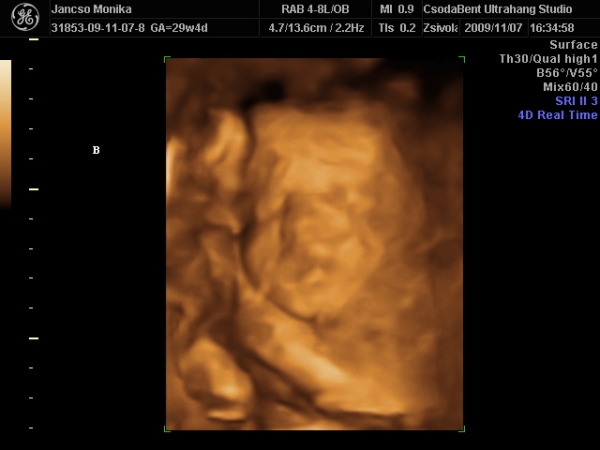

Na voltunk 4d-n mégis, a minimanóban ahol kiderült, hogy a szonográfus meg a férjem ismerik egymást, szóval biztos vagyok benne, hogy mindent megpróbált, de nem lettek jó képek talán 2 héttel korábban kellett volna mennünk

azért rakok be képeket

Kép

de nem is tudom ki kicsoda, ugyhogy most lehet hogy a két kép uarról a babáról van

ő a másik baba vagy nem :D :oops: